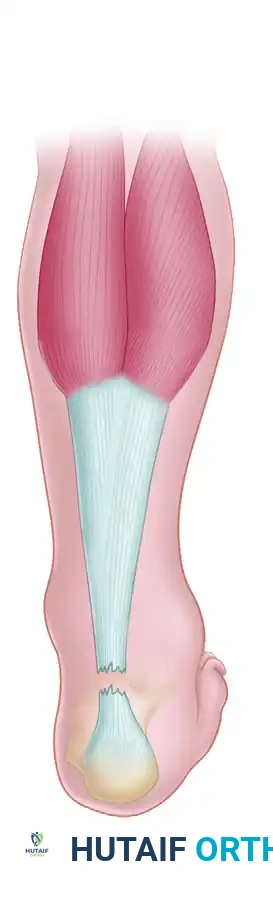

Surgical Management: V-Y Advancement Technique

For neglected ruptures with moderate defects (typically 2 to 5 cm) where the distal stump is robust and the proximal muscle belly retains adequate excursion, a V-Y aponeurotic advancement (often associated with the Abraham and Pankovich technique) is a highly effective strategy.

Step-by-Step V-Y Advancement

Incision and Exposure: A standard posteromedial incision is utilized to expose the ruptured ends. The fibrotic scar tissue is radically excised back to healthy, organized collagen bundles.

Design of the V-Flap: Proximal to the rupture, an inverted "V" incision is made through the gastrocnemius aponeurosis. The apex of the "V" is directed proximally. The length of the arms of the "V" must be at least 1.5 to 2 times the length of the defect to allow adequate distal excursion.

Advancement and Y-Repair: The aponeurotic flap is advanced distally, bridging the defect. The proximal "V" defect is then closed in a "Y" configuration. The advanced distal end of the flap is anastomosed end-to-end with the distal Achilles stump using heavy, non-absorbable core sutures (e.g., Krackow technique).